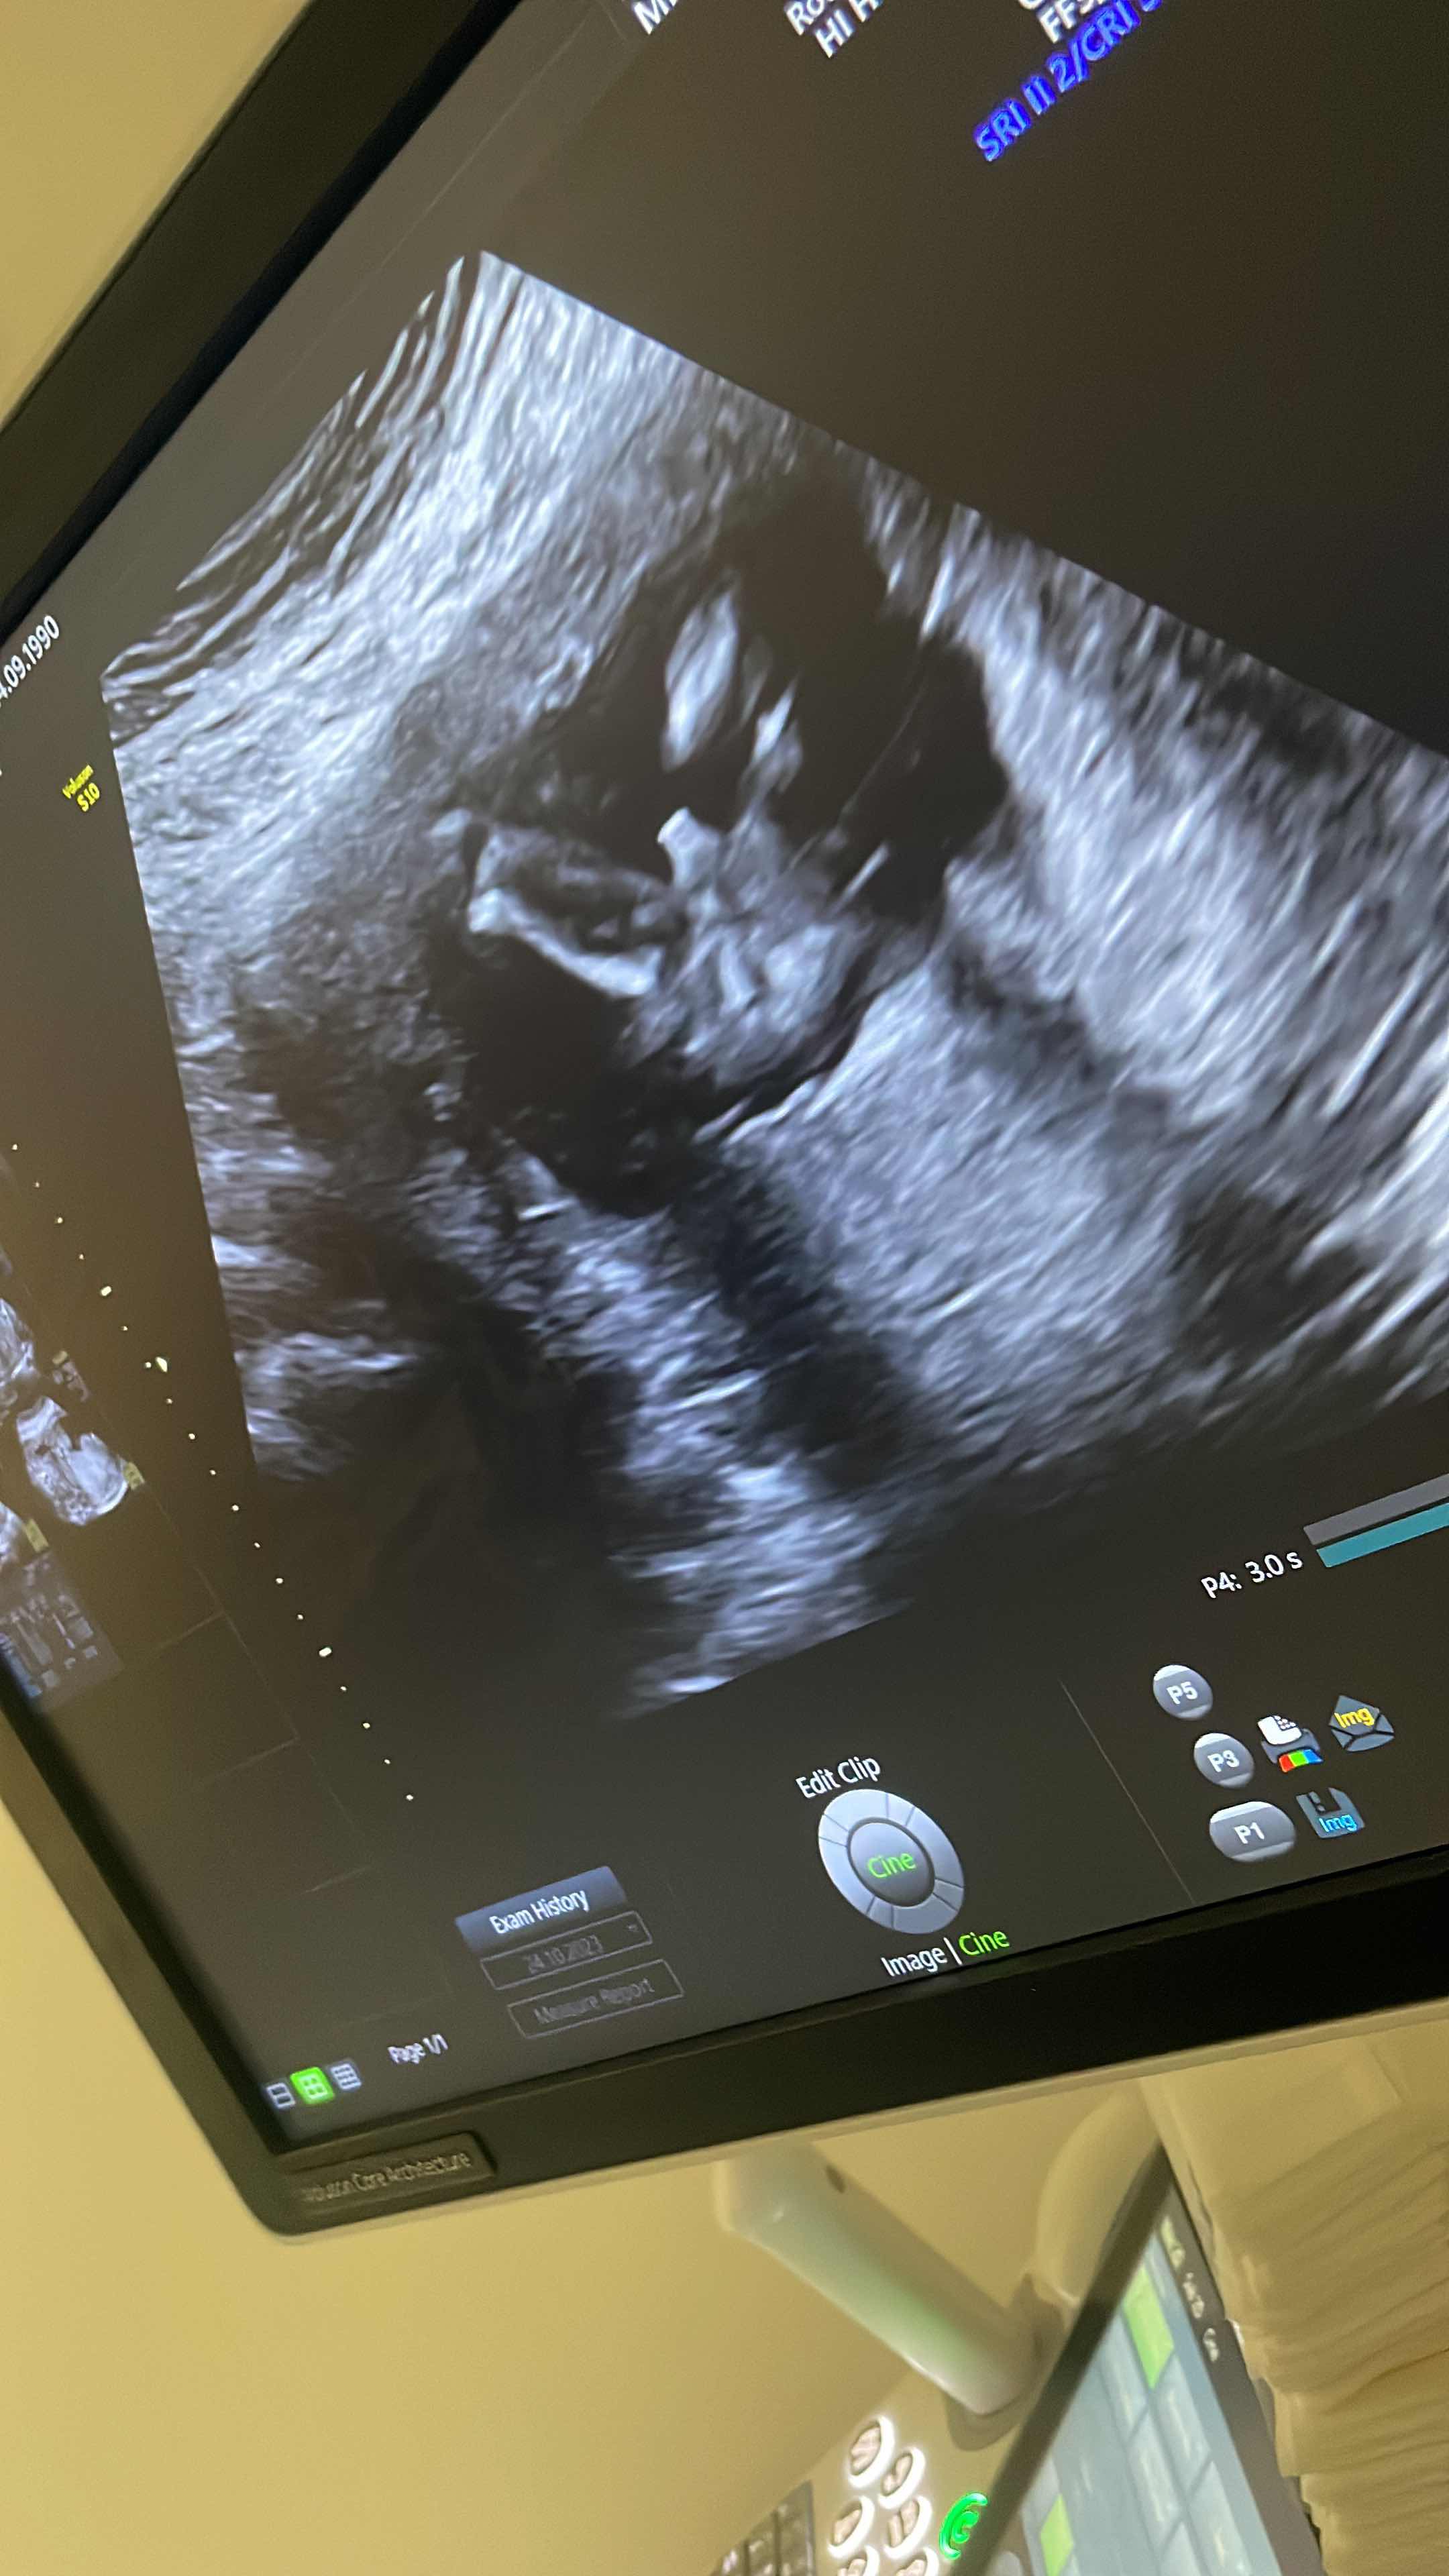

ثراءة صور سونار ذكر او انثى